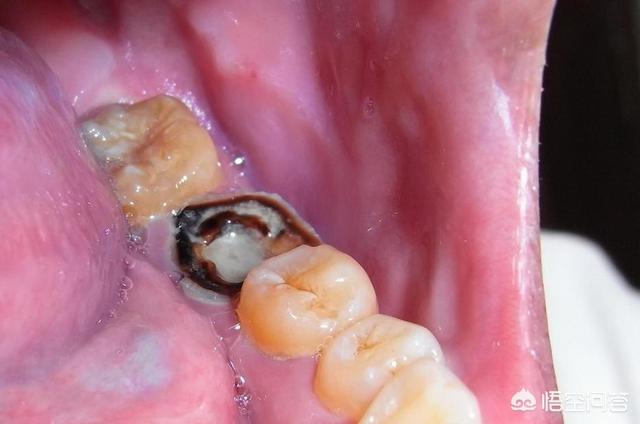

左の口の下隅にある2本の大きな歯が腐っているのは、歯が細菌によって深刻に腐敗していることを示している。歯髄が細菌の損傷によって感染し、歯髄の炎症の急性発作を引き起こしている可能性があり、歯が腐っていても歯を抜くことはできない。

例えば、最も一般的な根管治療は、歯髄炎や歯髄壊死があり、最初に病気の歯髄を除去することであり、第一は、歯痛の問題を解決することができ、第二は、ポーセレンクラウンを着用する歯の修復に便利です。

1、残根が完全であるかどうかによって、歯根が完全であれば、歯冠修復を行うことができ、歯根さえ腐っていれば、抜かなければならず、根管治療と相対する歯冠修復はより複雑であり、根管残根の歯髄を除去する検査を撮影することに加えて、黒い石灰沈着物の近くの歯根はより多く、また、歯周スケーリングを行う必要があります。